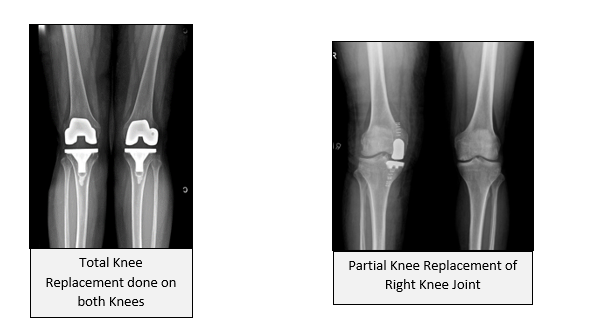

If you compare the two pictures given below, on the left it shows loss of space throughout the knee on the right it shows loss of space only in confined area of the knee. In the right-side picture, the loss of cartilage is confined to inner part of the knee, or also called as medial tibio-femoral joint. So, in selected patients with the kind of picture as shown on the right side, one can think of performing Partial Knee Replacement. Fortunately, large number of cases in our country, are eligible for Partial Knee Replacement or Unicondylar Knee Replacement. Do ask your doctor if you are a candidate for Partial Knee Replacement, if you have been advised Total Knee Replacement. Remember only your surgeon can decide this, not you!!!!